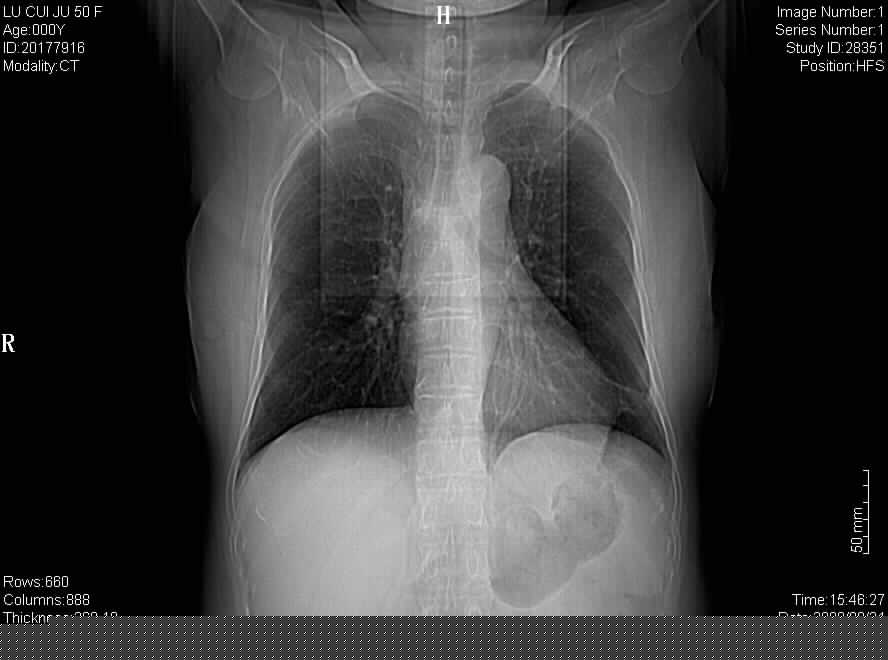

标题: CT15870:F50Y,纵膈占位,是不是胸腺瘤,请各位高手讨论。

临床表现为重症肌无力;ct增强扫描可见前纵膈胸腺部位弥漫性簇状软组织节结灶,不知道是不是胸腺瘤,请各位高手讨论。

胸腺外缘稍向外突,未见确切占位改变。结合临床考虑胸腺增生可能性大。